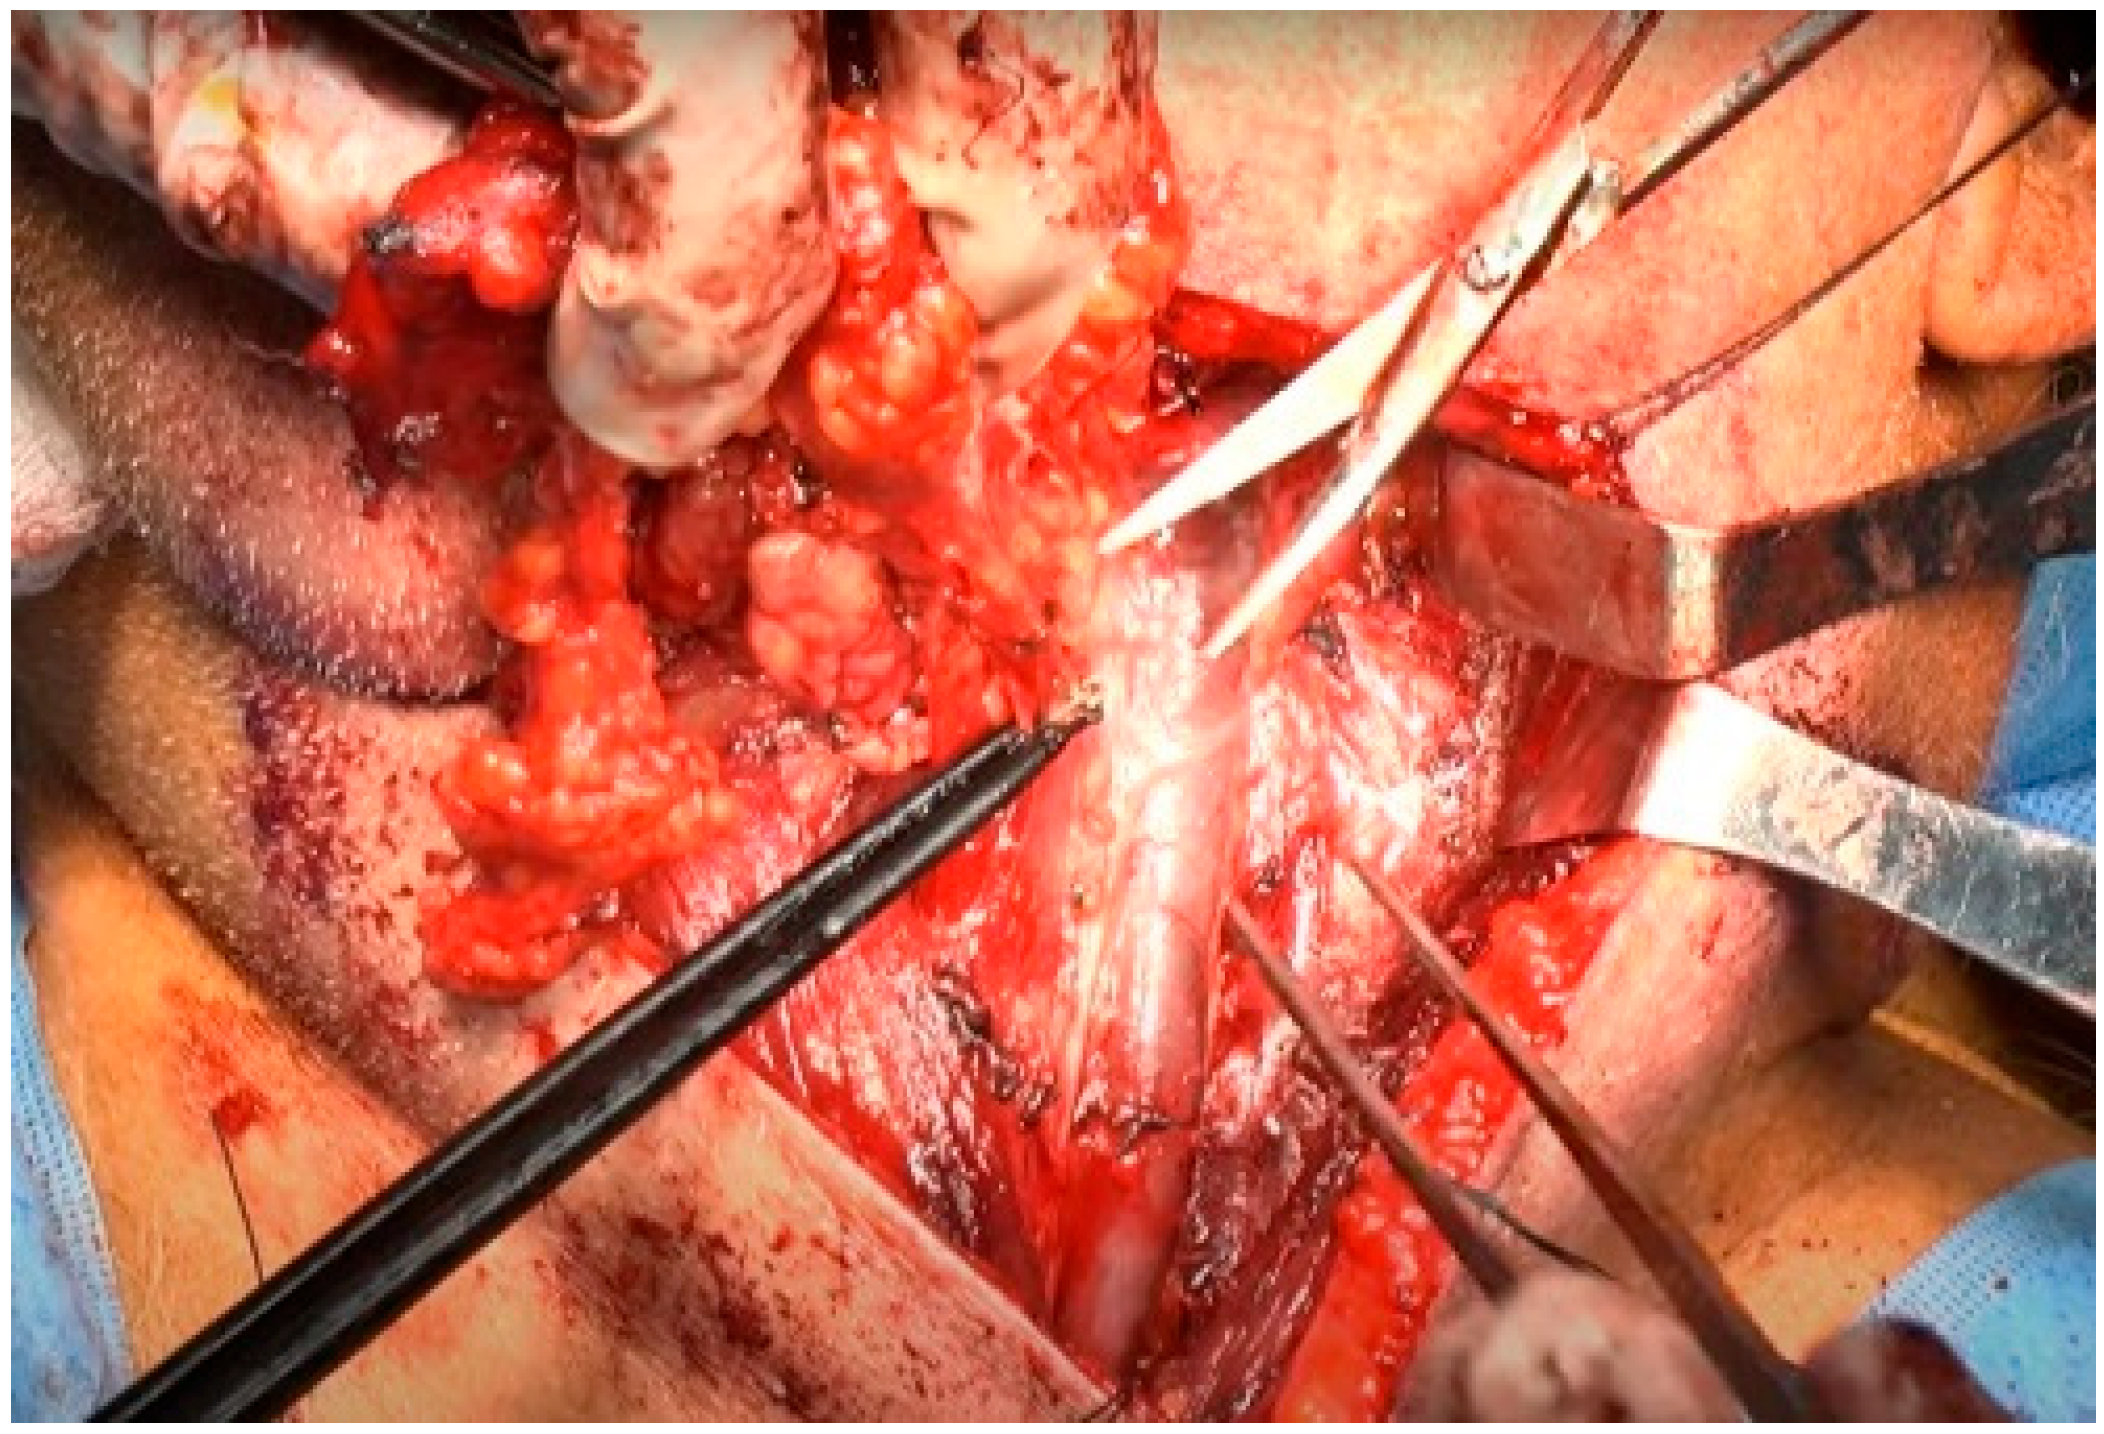

At this point, the neck dissection was complete, and the facial artery was identified, which helped differentiate between the internal and external carotid arteries. By opening the carotid sheath using curved pean forceps, the common carotid artery was made visible. Tracing upward led to the bifurcation of the carotid artery. The presence of branches serves as a characteristic feature of the external carotid artery. The superior thyroid artery, the first branch of the external carotid artery, originates below the level of the greater horn of the hyoid bone. The lingual artery, closely associated with the hyoid bone, originates from the external carotid artery above the level of the greater horn [28]. The root of the facial artery is located obliquely beneath the digastric and stylohyoid muscles [29,30]. These branches were used to identify the external carotid artery. After separating the external carotid artery from the internal carotid artery and vagus nerve, a Rummel tourniquet was used to restrict the external carotid artery and control bleeding (Figure 10).

Figure 10.

Rummel tourniquet restriction of the left ECA.